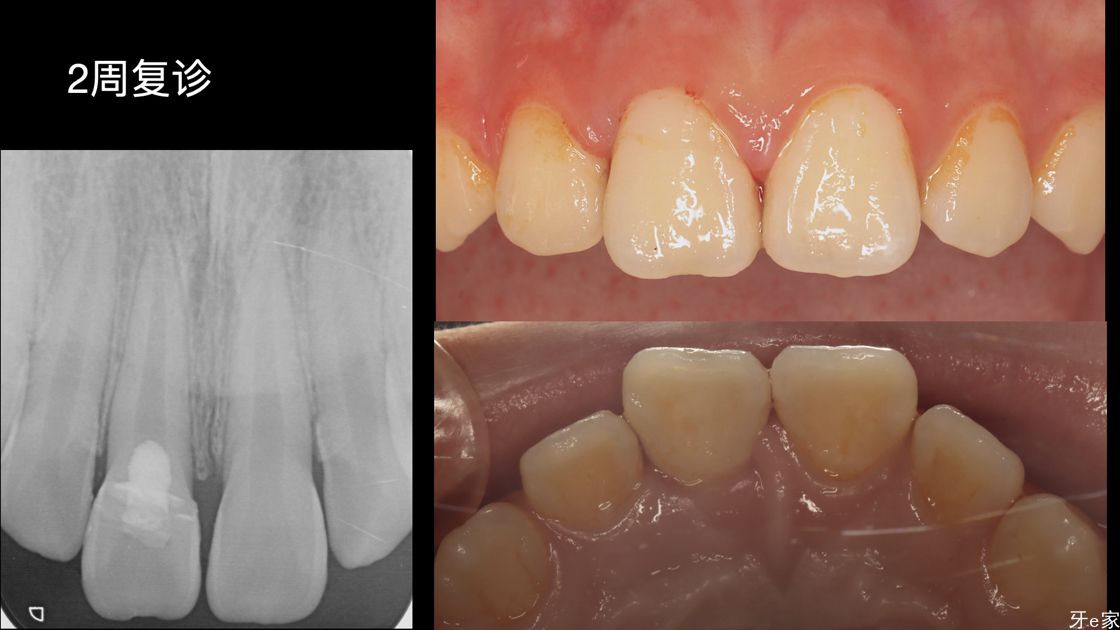

术后总结